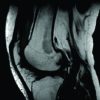

A 12-year-old girl complained of knee pain and clicking that had persisted for 3 months without trauma. Physical examination of the patient revealed limited extension (range of motion is 20°–135°) and a positive McMurray test on the lateral side. An enlarged lateral joint space with high signal intensity in the region of the lateral meniscus was observed on magnetic resonance imaging (MRI) (Fig. 1).